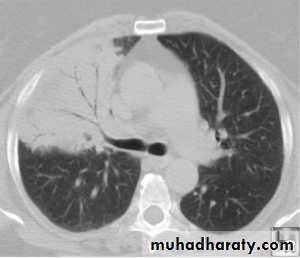

Chest X-ray shows mottled opacities in both lung fields, chiefly in the lower zones (Bronchopneumonia).

• Bronchopneumonia: Typically patchy and segmental shadowing

• Complications: Para-pneumonic effusion, intrapulmonary abscess or empyema